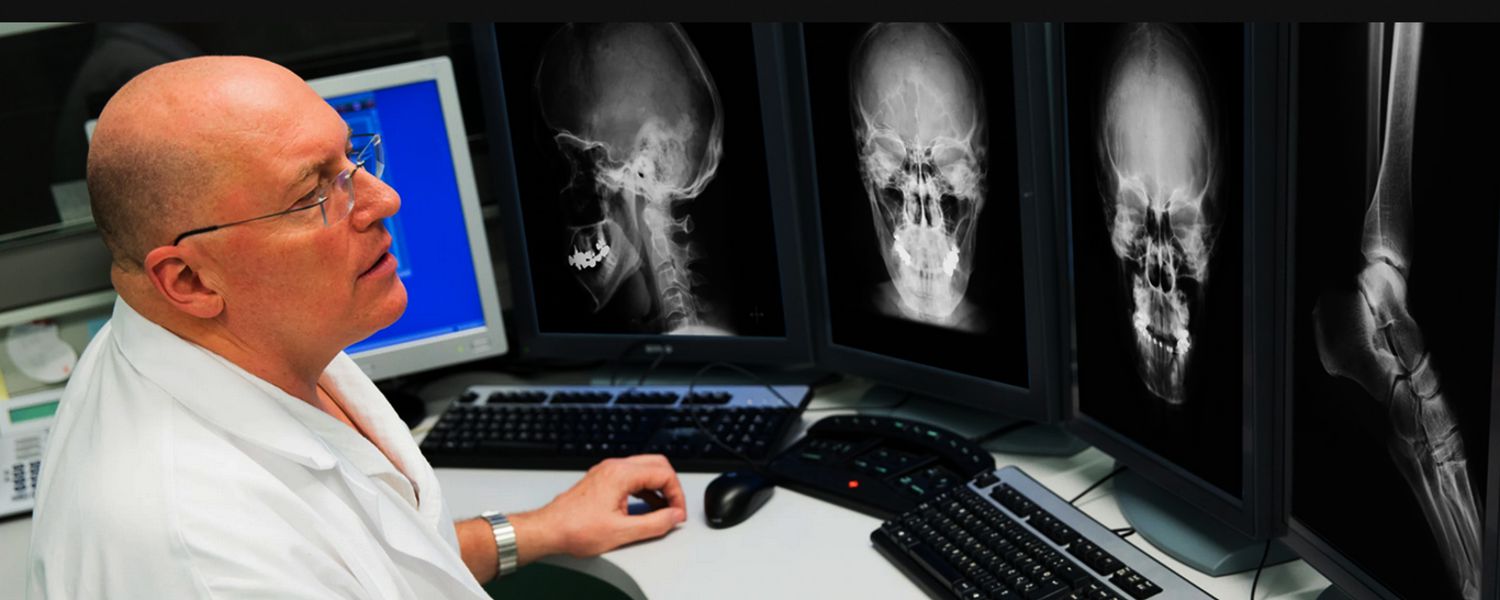

¿Qué son los Rayos X?

Los Rayos X son un tipo de radiación llamada ondas electromagnéticas. Estos son capaces de mostrar el interior del cuerpo en distintos tonos de blanco y negro.

Su uso más frecuente es para ver fracturas aunque también tiene otros usos como por ejemplo detectar neumonías o el cáncer de mama.